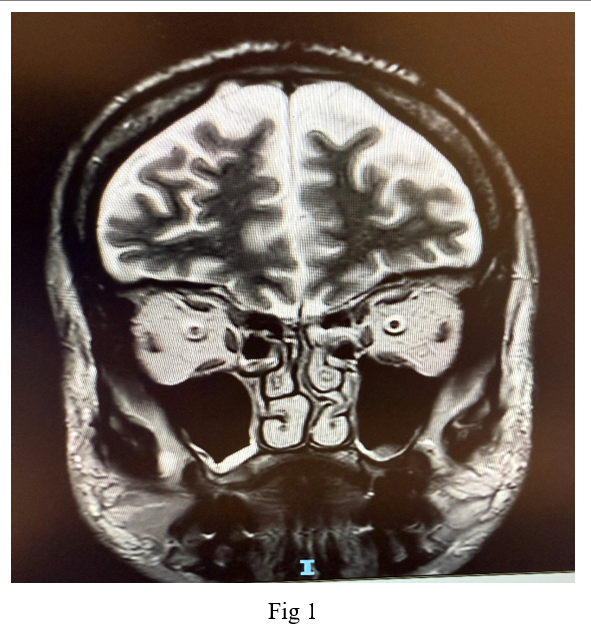

Imaging studies, including a native CT scan of the brain, MRI of the brain, and MRI of the orbit without contrast, revealed no pathological findings. Additionally, laboratory tests, including a complete blood count, erythrocyte sedimentation rate, C-reactive protein, fasting blood sugar, glycated hemoglobin, thyroid function tests, kidney function tests, B12 levels, blood glucose, and blood pressure, were all within normal ranges. Following a neurological consultation, he was diagnosed with cluster headache associated with oculomotor nerve palsy.

In this case, diabetic oculomotor nerve palsy was considered as a possible differential diagnosis; however, due to the classic symptoms of cluster headache and the fact that the MRI did not show any signs of inflammation or thickening of the oculomotor nerve in the cavernous sinus—characteristic of microvascular damage caused by diabetes—this differential diagnosis is unlikely.

Neuroimaging, such as Cranial MRI, is essential to rule out structural abnormalities, particularly in patients with symptoms resembling other headache types or conditions like pituitary tumors. Distinguishing cluster headaches from other trigeminal autonomic cephalalgias and primary headache disorders is crucial for appropriate management.

Figure 2